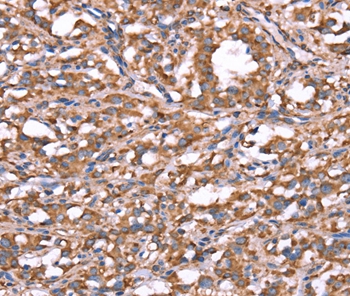

Immunohistochemical analysis of paraffin-embedded Human thyroid cancer tissue using #37577 at dilution 1/20.

Immunohistochemical analysis of paraffin-embedded Human brain tissue using #37577 at dilution 1/20.